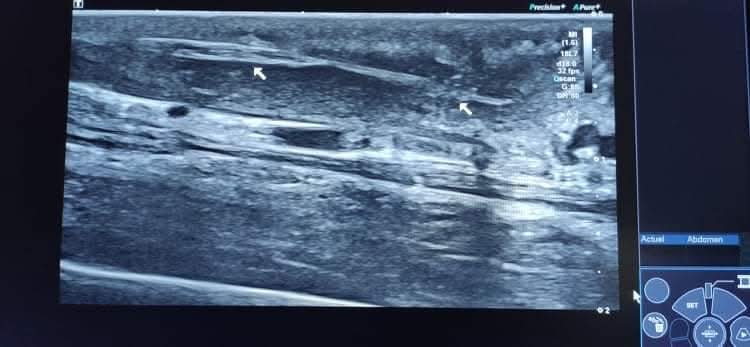

A l’examen, la zone au-dessus des doigts est gonflée et une échographie réalisée par le Dr Pommier met en évidence un corps étranger végétal sournoisement allongé sous la peau à au moins 5 cm de son point d’entrée situé entre les doigts.